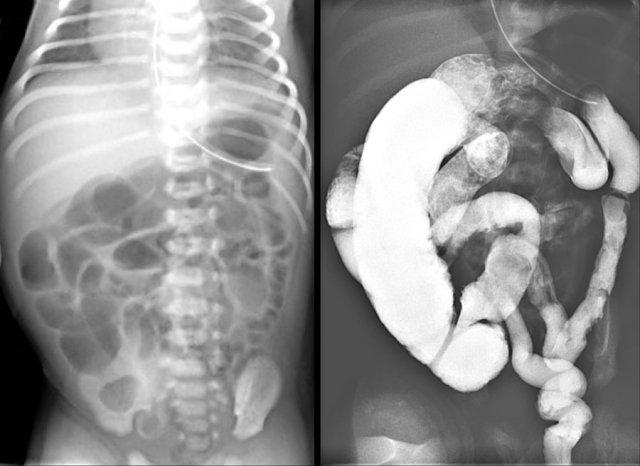

Đây là hai trường hợp tắc ruột phân su.

Có hình ảnh đại tràng nhỏ và nhiều viên phân su ở đoạn ruột non xa (mũi tên).